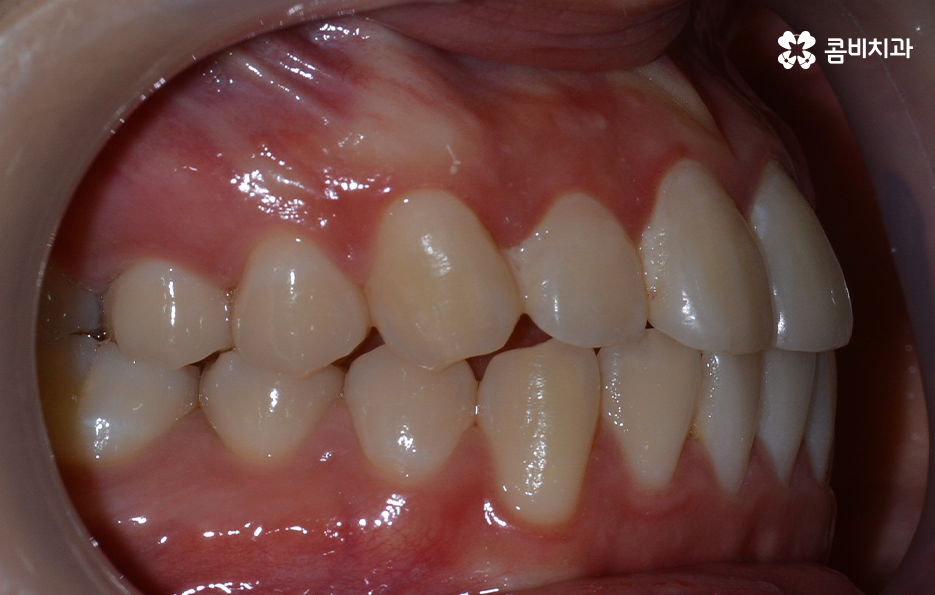

출처 아카이브 열기치아교정의 목적은 다양하지만 돌출입을 개선하고자 하는 목적성을 갖는 경우 발치가 필요한 경우가 대부분이라고 할 수 있는데요. 그 이유는 입이 나와 있는 돌출입을 개선하기 위해서는 앞니 부분이 뒤 쪽으로 들어가야 돌출입이 개선되기 때문인데 치아를 안쪽으로 이동시키기 위한 공간 확보를 위해 발치가 필요한 경우가 많은 거예요.

돌출입을 개선하기 위한 교정 치료의 사례에도 돌출입발치교정 사례가 많은 이유도 치아의 발치를 통해 앞니를 후방 이동시키는 치아 교정의 원리가 있기 때문이라고 설명할 수 있어요

돌출입에 대한 고민으로 치아교정을 고민하신다면 치아교정 후 결과에 있어서 얼굴 변화에 대한 부분이 더 중요하게 느껴질 수 있어요. 치아교정을 통해서 얼굴은 변화할 수 있기 때문에 교정 전에도 3D CT나 모르페우스 등과 같은 장비로 3D 예측을 활용하고 있는데요

보통 치아교정을 통해 눈에 띄게 얼굴 변화를 느끼게 되는 경우는 쉽게 말해 발치를 통한 교정으로 볼 수 있어요. 그 이유는 치아를 발치하게 되면 발치한 만큼의 공간이 악궁에서 축소가 되기 때문에 그로 인해 얼굴라인이 갸름하게 변하게 되거나 돌출입발치교정 같이 돌출입의 개선이 되는 거예요